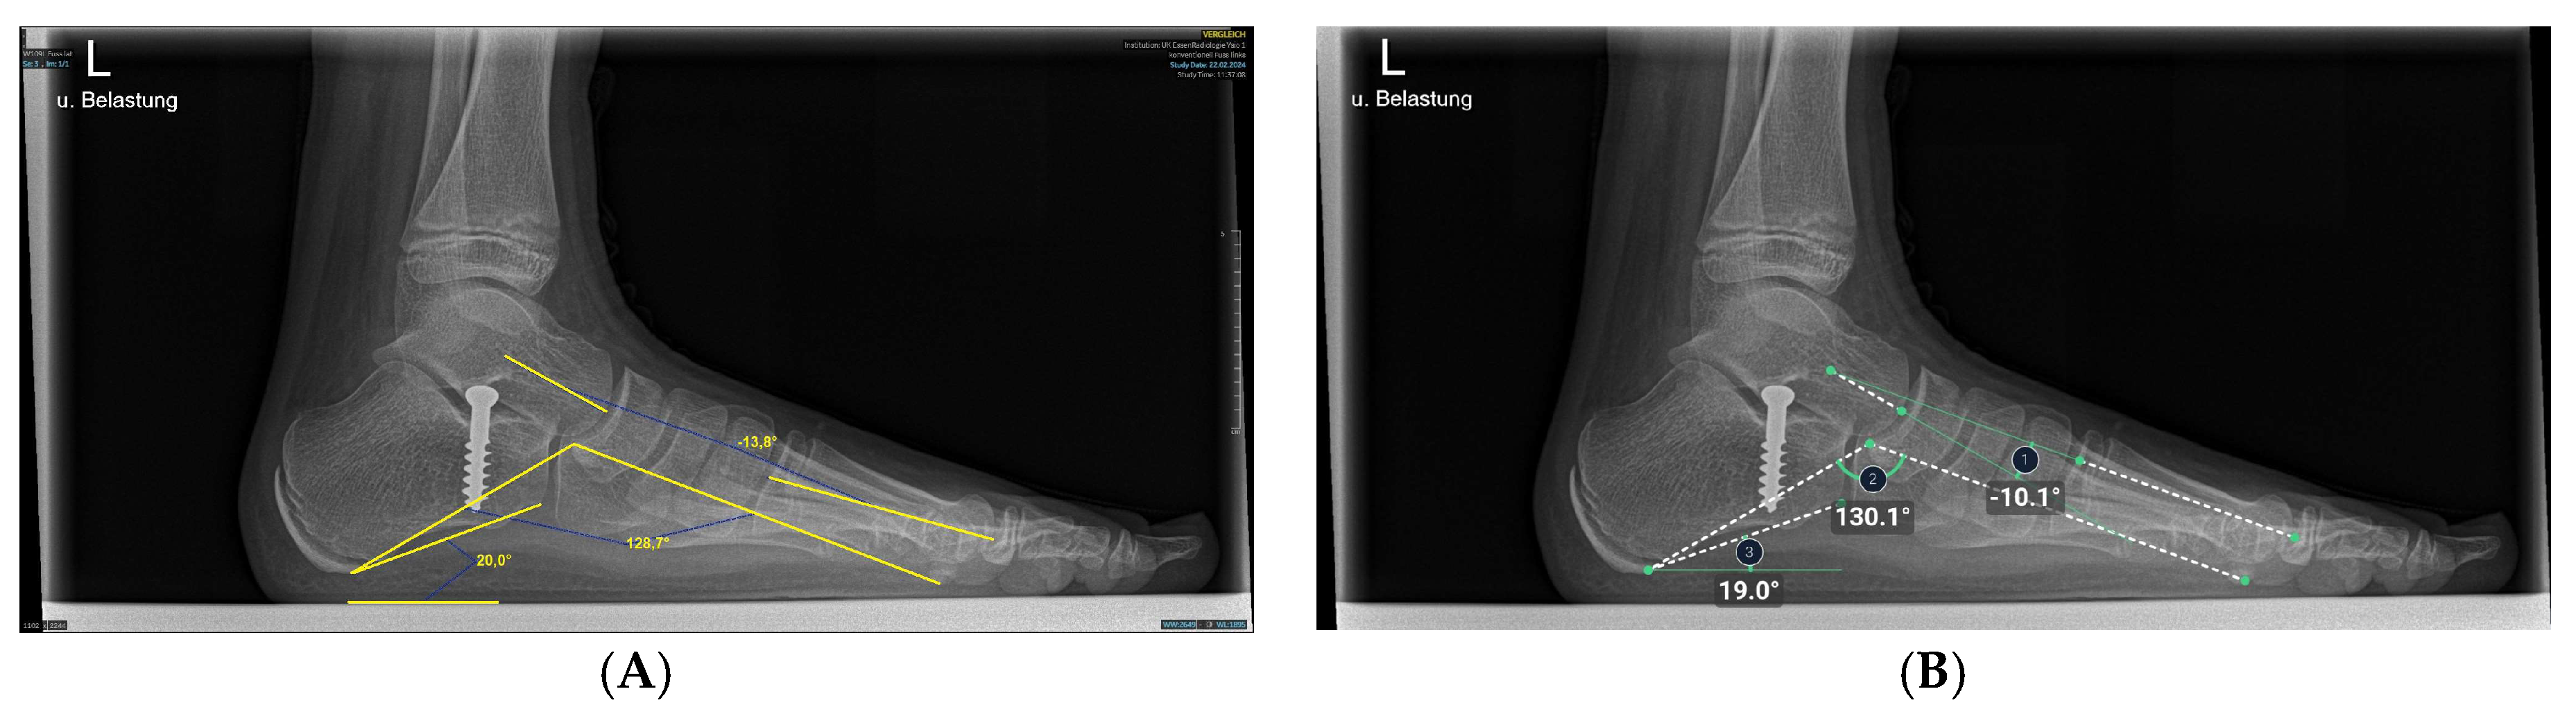

2.5. Anatomic Definitions

At this point, the AI system used was able to measure three angles each of the lateral and dorsoplantar projection (Figure 2 and Figure 3). The talus-1st metatarsal angle and all three angles in the dorsoplantar plane were defined by the intersection of axes. Axes for angle measurements were mechanically defined as lines connecting the center of the bone head and the center of the bone base [30,31]. The talus-1st metatarsal angle was determined by the intersection of the axis of the first metatarsal and a line intersecting the head and neck of the talus [23,32]. (Figure 2). The medial arch angle was measured by a line joining the lowest point of the medial sesamoid with the lowest point of the talonavicular joint and from there a line to the lower edge of the calcaneus [23,32]. The calcaneus inclination angle was defined by the intersection of a line drawn from the inferior cortex of the calcaneus to the inferior corner of the calcaneus, which belongs to the calcaneocuboid joint with the horizontal axis [23]. Physiological values were −4° to 4 ° for the talus-first metatarsal angle. For 8-year-old children, 5 ° was given as the standard values at this age [6]. The normal value was 120 ° to 130° for the medial arch angle and 11 ° to 24 ° for the calcaneal inclination angle on X-rays of immature children [6,33].

The hallux valgus angle is determined by the axis of the first metatarsal bone that of the proximal phalanx [23,32].

Having intersected the axis of the first metatarsal bone with the axis of the second metatarsal bone, the 1st-2nd metatarsal angle was obtained [23,32].

The intersection of the axes of the 1st metatarsal and 5th metatarsal resulted in the third and last angle examined, the 1st-5th metatarsal angle [23].

Figure 2. Illustration of talus-1st metatarsal angle, medial arch angle, and calcaneus inclination angle measurements on X-ray images in the lateral plane. (A) Manual measurement exemplary. The same X-ray image was processed by the AI. (B) Angles calculated by AI.